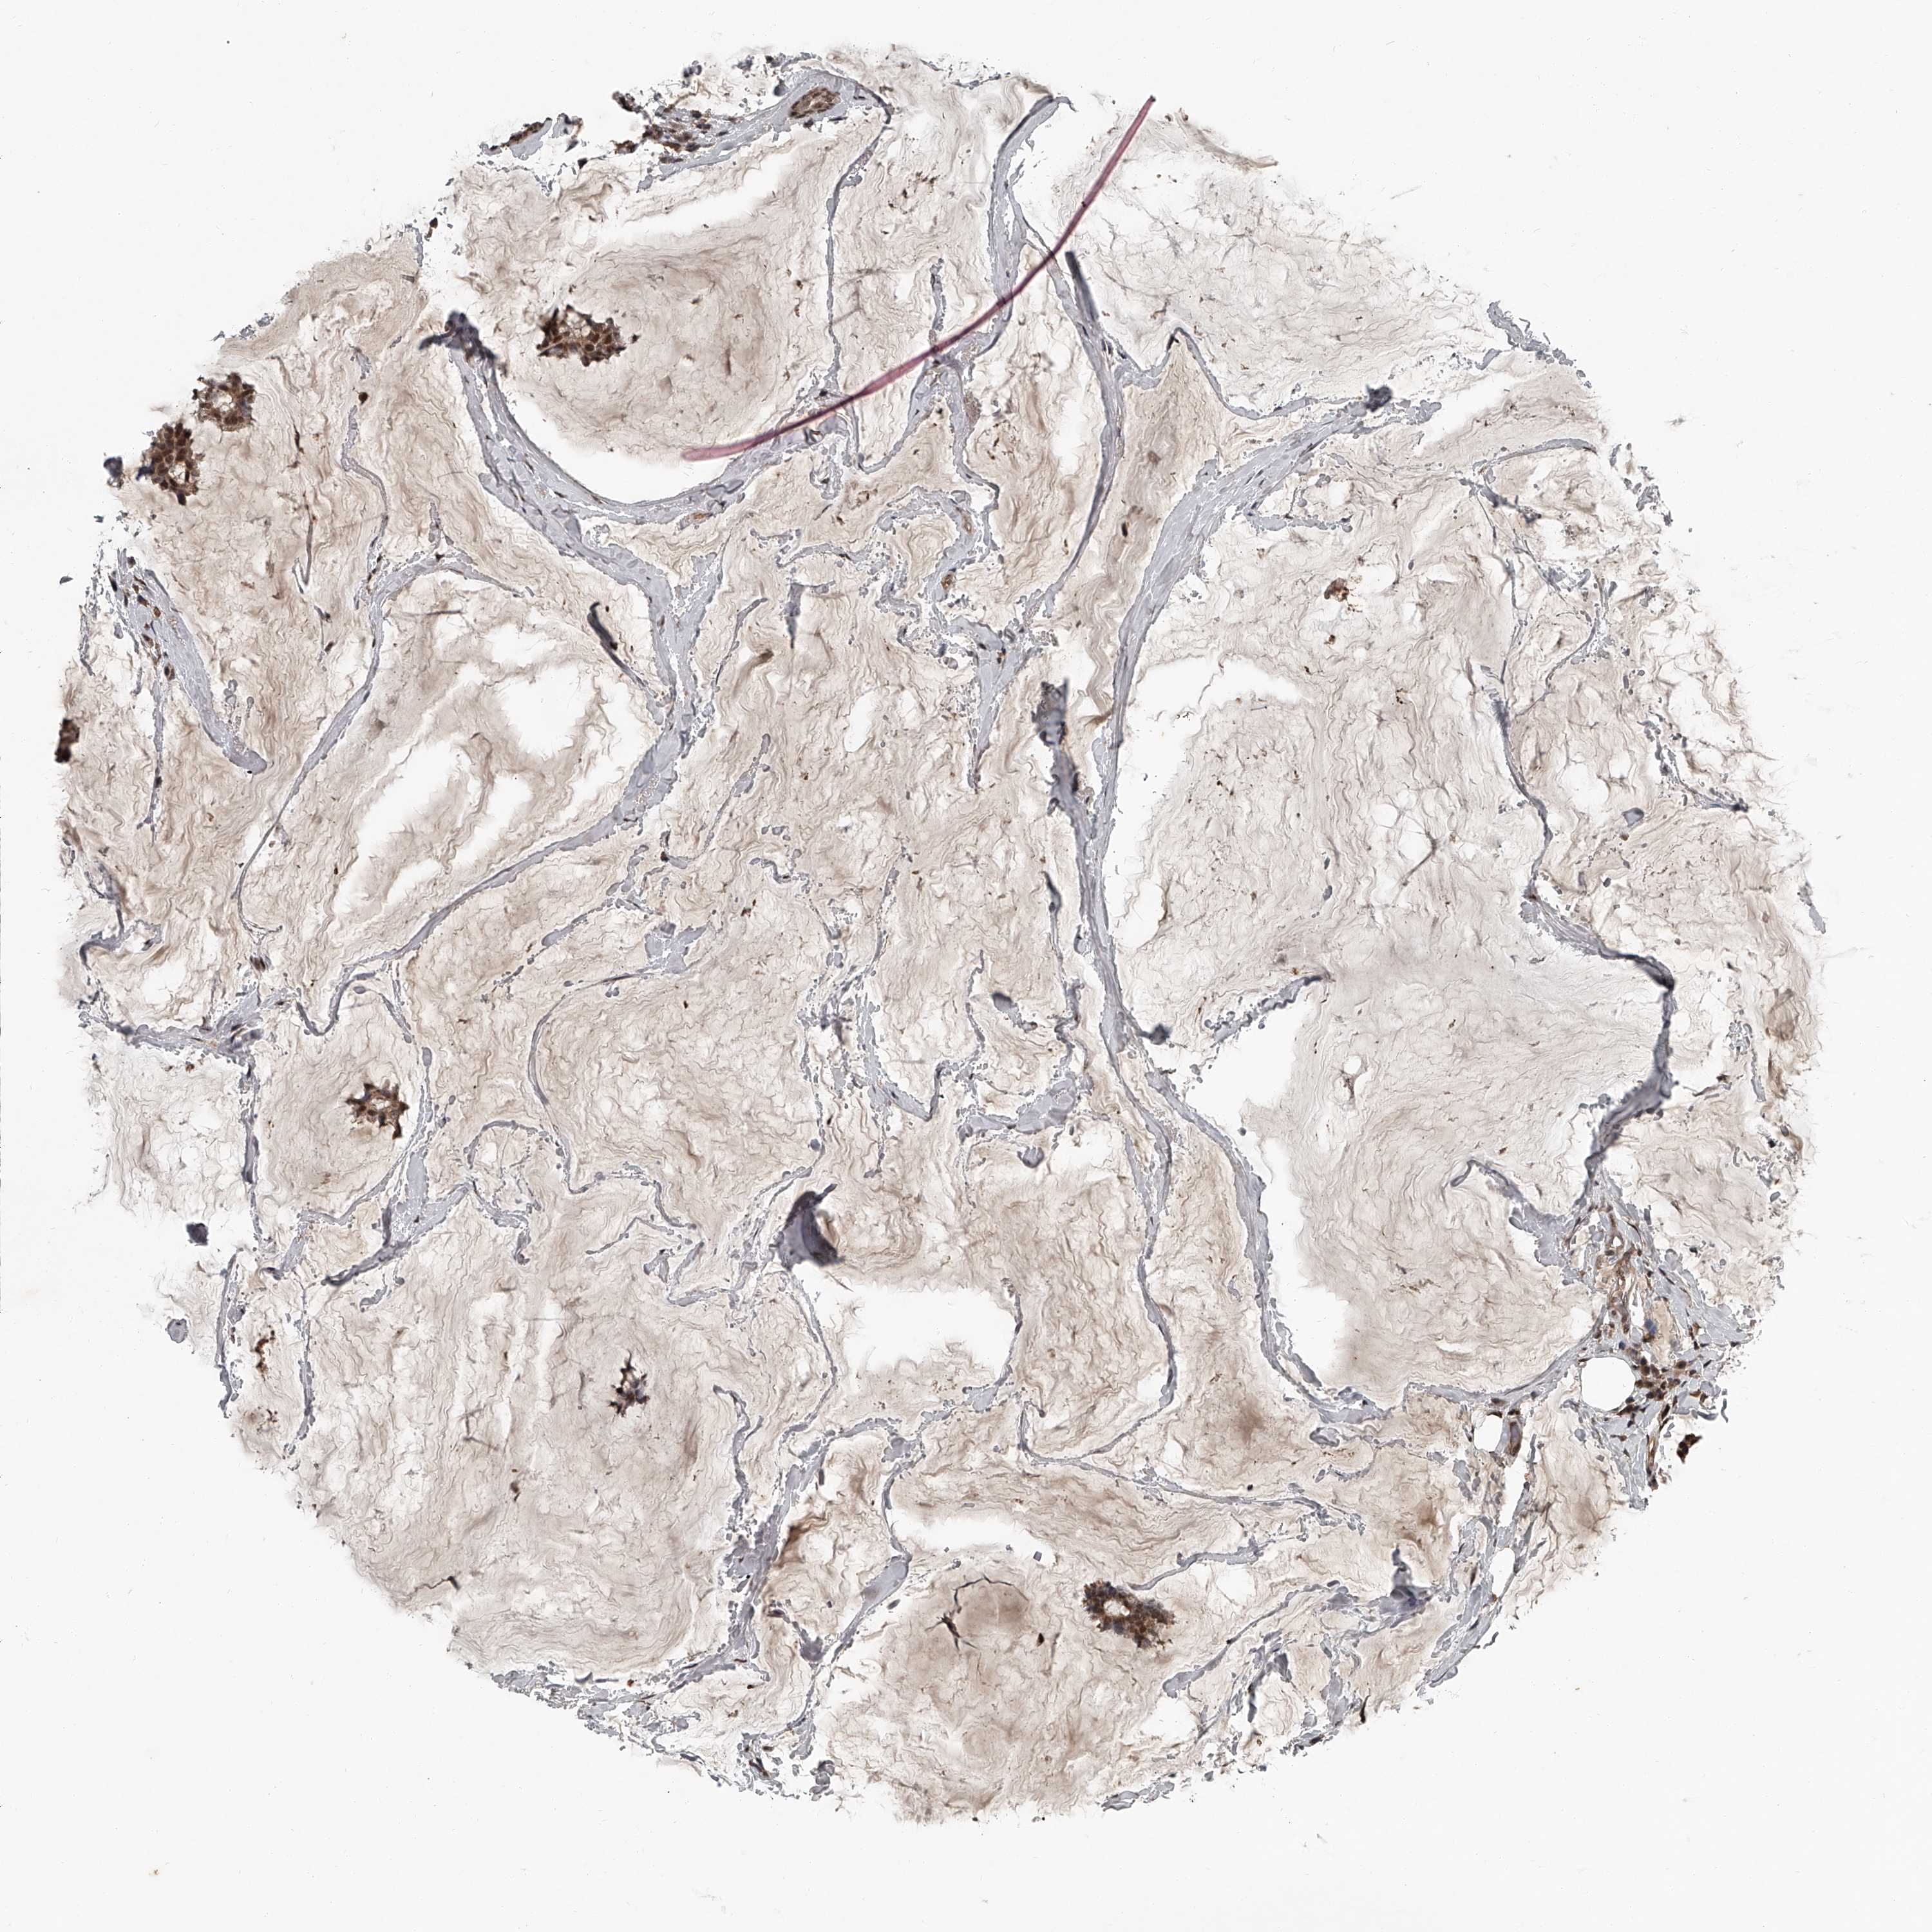

CANCER BREAST CANCER Show tissue menu

BRCA TCGA BRCA VALIDATION PROTEIN EXPRESSION